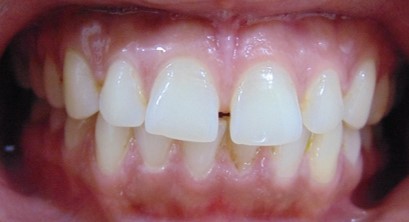

Divya Patil, 28Y, Duration - 6Months

Before

After

Image 1